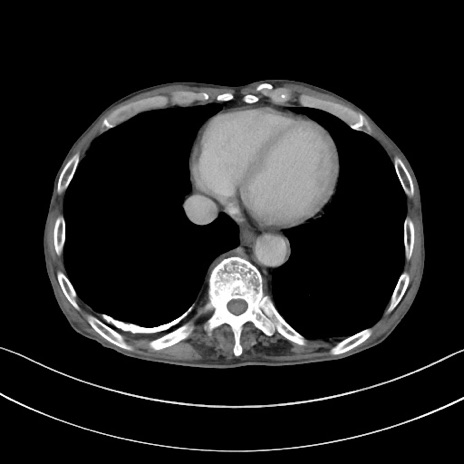

症例3(横断像)

【症例】 70歳代男性

【主訴】右鼠径部腫瘤、疼痛

【現病歴】本日朝より上記主訴あり、受診。

【既往歴】膀胱癌にて膀胱全摘、両側尿管皮膚瘻

【データ】WBC 5600、CRP 0.56